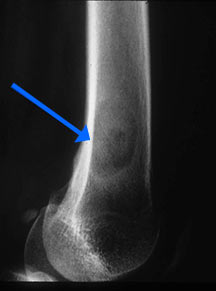

- May arise from any bone and any site within a bone (epiphyseal, metaphyseal, diaphyseal)

- Radiographically variable appearance: may appear benign (geographic) or malignant (permeative or moth eaten)

Radiographic Presentation